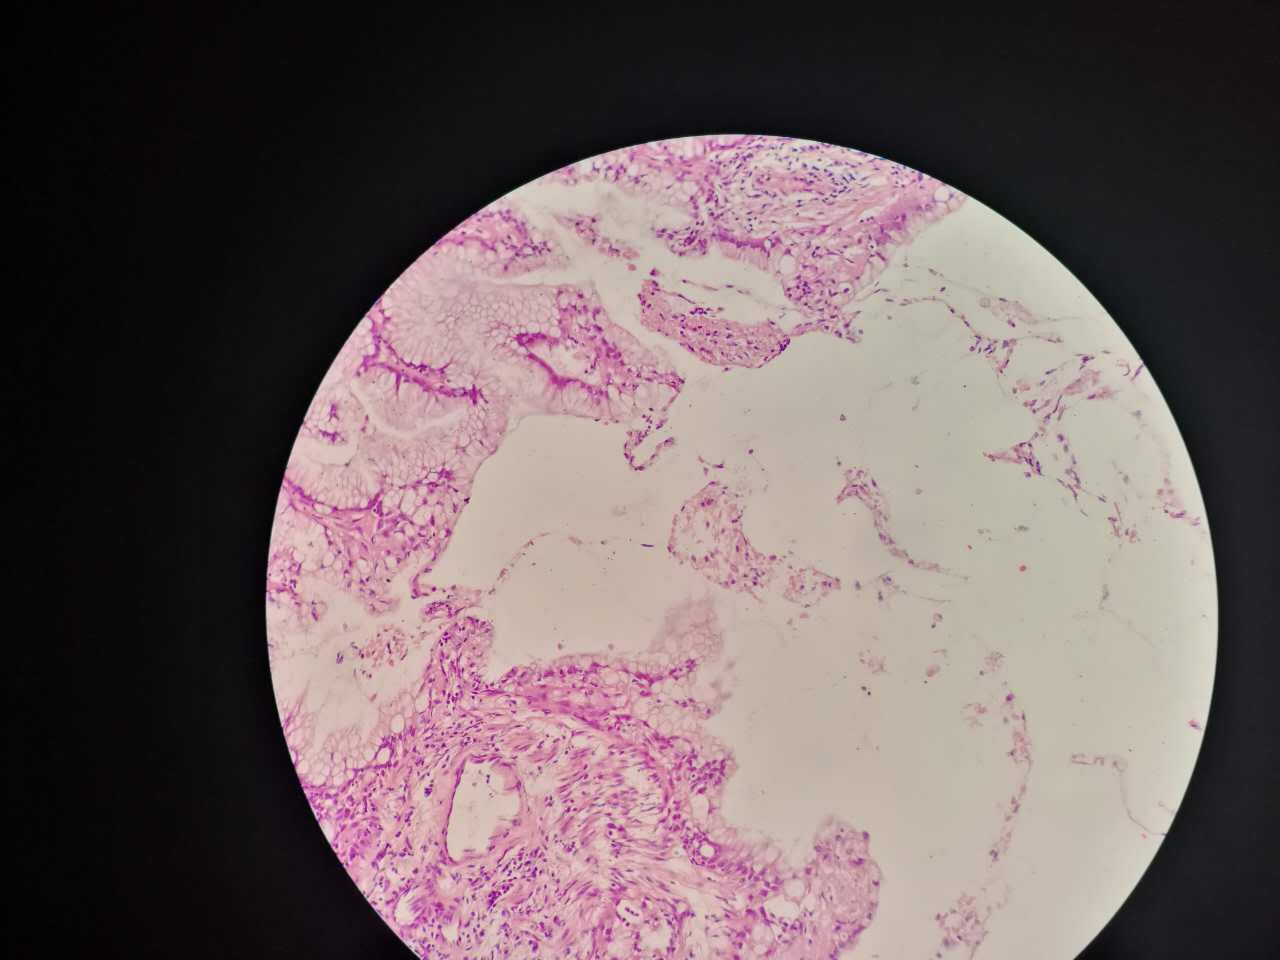

粘液型腺癌

粘液型腺癌是原发肺腺癌中的一种特殊类型

细胞内外含较多粘液

粘液型腺癌,细胞内粘液多,有点儿像支气管的粘液腺

单纯的粘液腺,没有浆液腺

细胞外粘液湖

粘液腺癌起源于细支气管和肺泡

这一幅的上方都是黏液湖

下方是正常肺泡

细胞内白颜色区是粘液,细胞外洋流样的也是粘液(湖)

黏液湖里可以飘着一些细胞,吞噬细胞及肿瘤细胞。

肿瘤细胞飘出去可以种植于肺泡上。

肿瘤细胞堆经常是离开的

中间这一团,整个都是飘过来种植长成这样

这在进展后期特别多见

早期飘散常很近

这个是早期结节状的粘液型腺癌

随着粘液近距离播散

早期粘液漂散也是近距离的,右侧肺泡里干净,没粘液,粘液产量有限,并且互相有黏连牵制。

所以结节性粘液腺癌边界一般较清楚